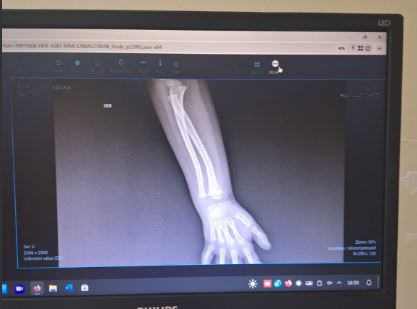

Un niño de tres años y cuatro meses, alumno del Jardín Maternal Authemo Aitue, ubicado en el barrio IPPV, habría sufrido una fractura en el brazo derecho bajo circunstancias que sus padres consideran sospechosas. La familia denunció una presunta agresión por parte de una docente y criticó la falta de transparencia de la institución.

Al ser trasladado al hospital, se confirmó que el niño presentaba una fractura en el radio del brazo derecho. Los padres aseguran que el pequeño mencionó haber sido agredido por una maestra, quien lo habría jalado del pelo y lanzado al suelo. Estas declaraciones llevaron a la familia a radicar una denuncia policial y a presentar una exposición ante el Ministerio de Nivel Inicial y la Fiscalía.